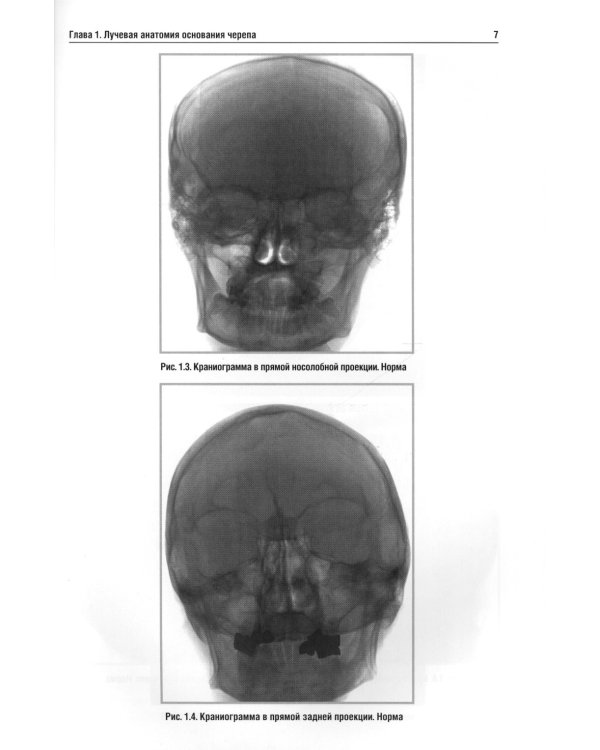

В учебном пособии изложена нормальная лучевая анатомия основания черепа по данным рентгенологического исследования, КТ и МРТ. Вторая и третья главы посвящены описанию лучевой семиотики наиболее часто встречающихся заболеваний основания черепа и мостомозжечкового угла, в которых представлены данные рентгенологического исследования, КТ и МРТ. Даются рекомендации по тактике лучевого исследования, приводится дифференциальная диагностика. Рассматриваются вопросы этиологии, патогенеза, морфологии и клинические проявления заболеваний. Для врачей, обучающихся по лучевой диагностике, нейрохирургии и неврологии. Пособие может быть рекомендовано для подготовки в системе последипломного профессионального образования.| Издательство | Элби |